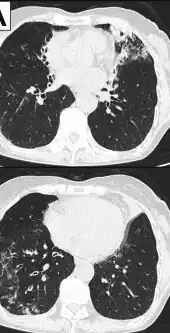

- Image indicate bronchodilation, centrilobular granular shadow, and consolidation

- Chest radiograph